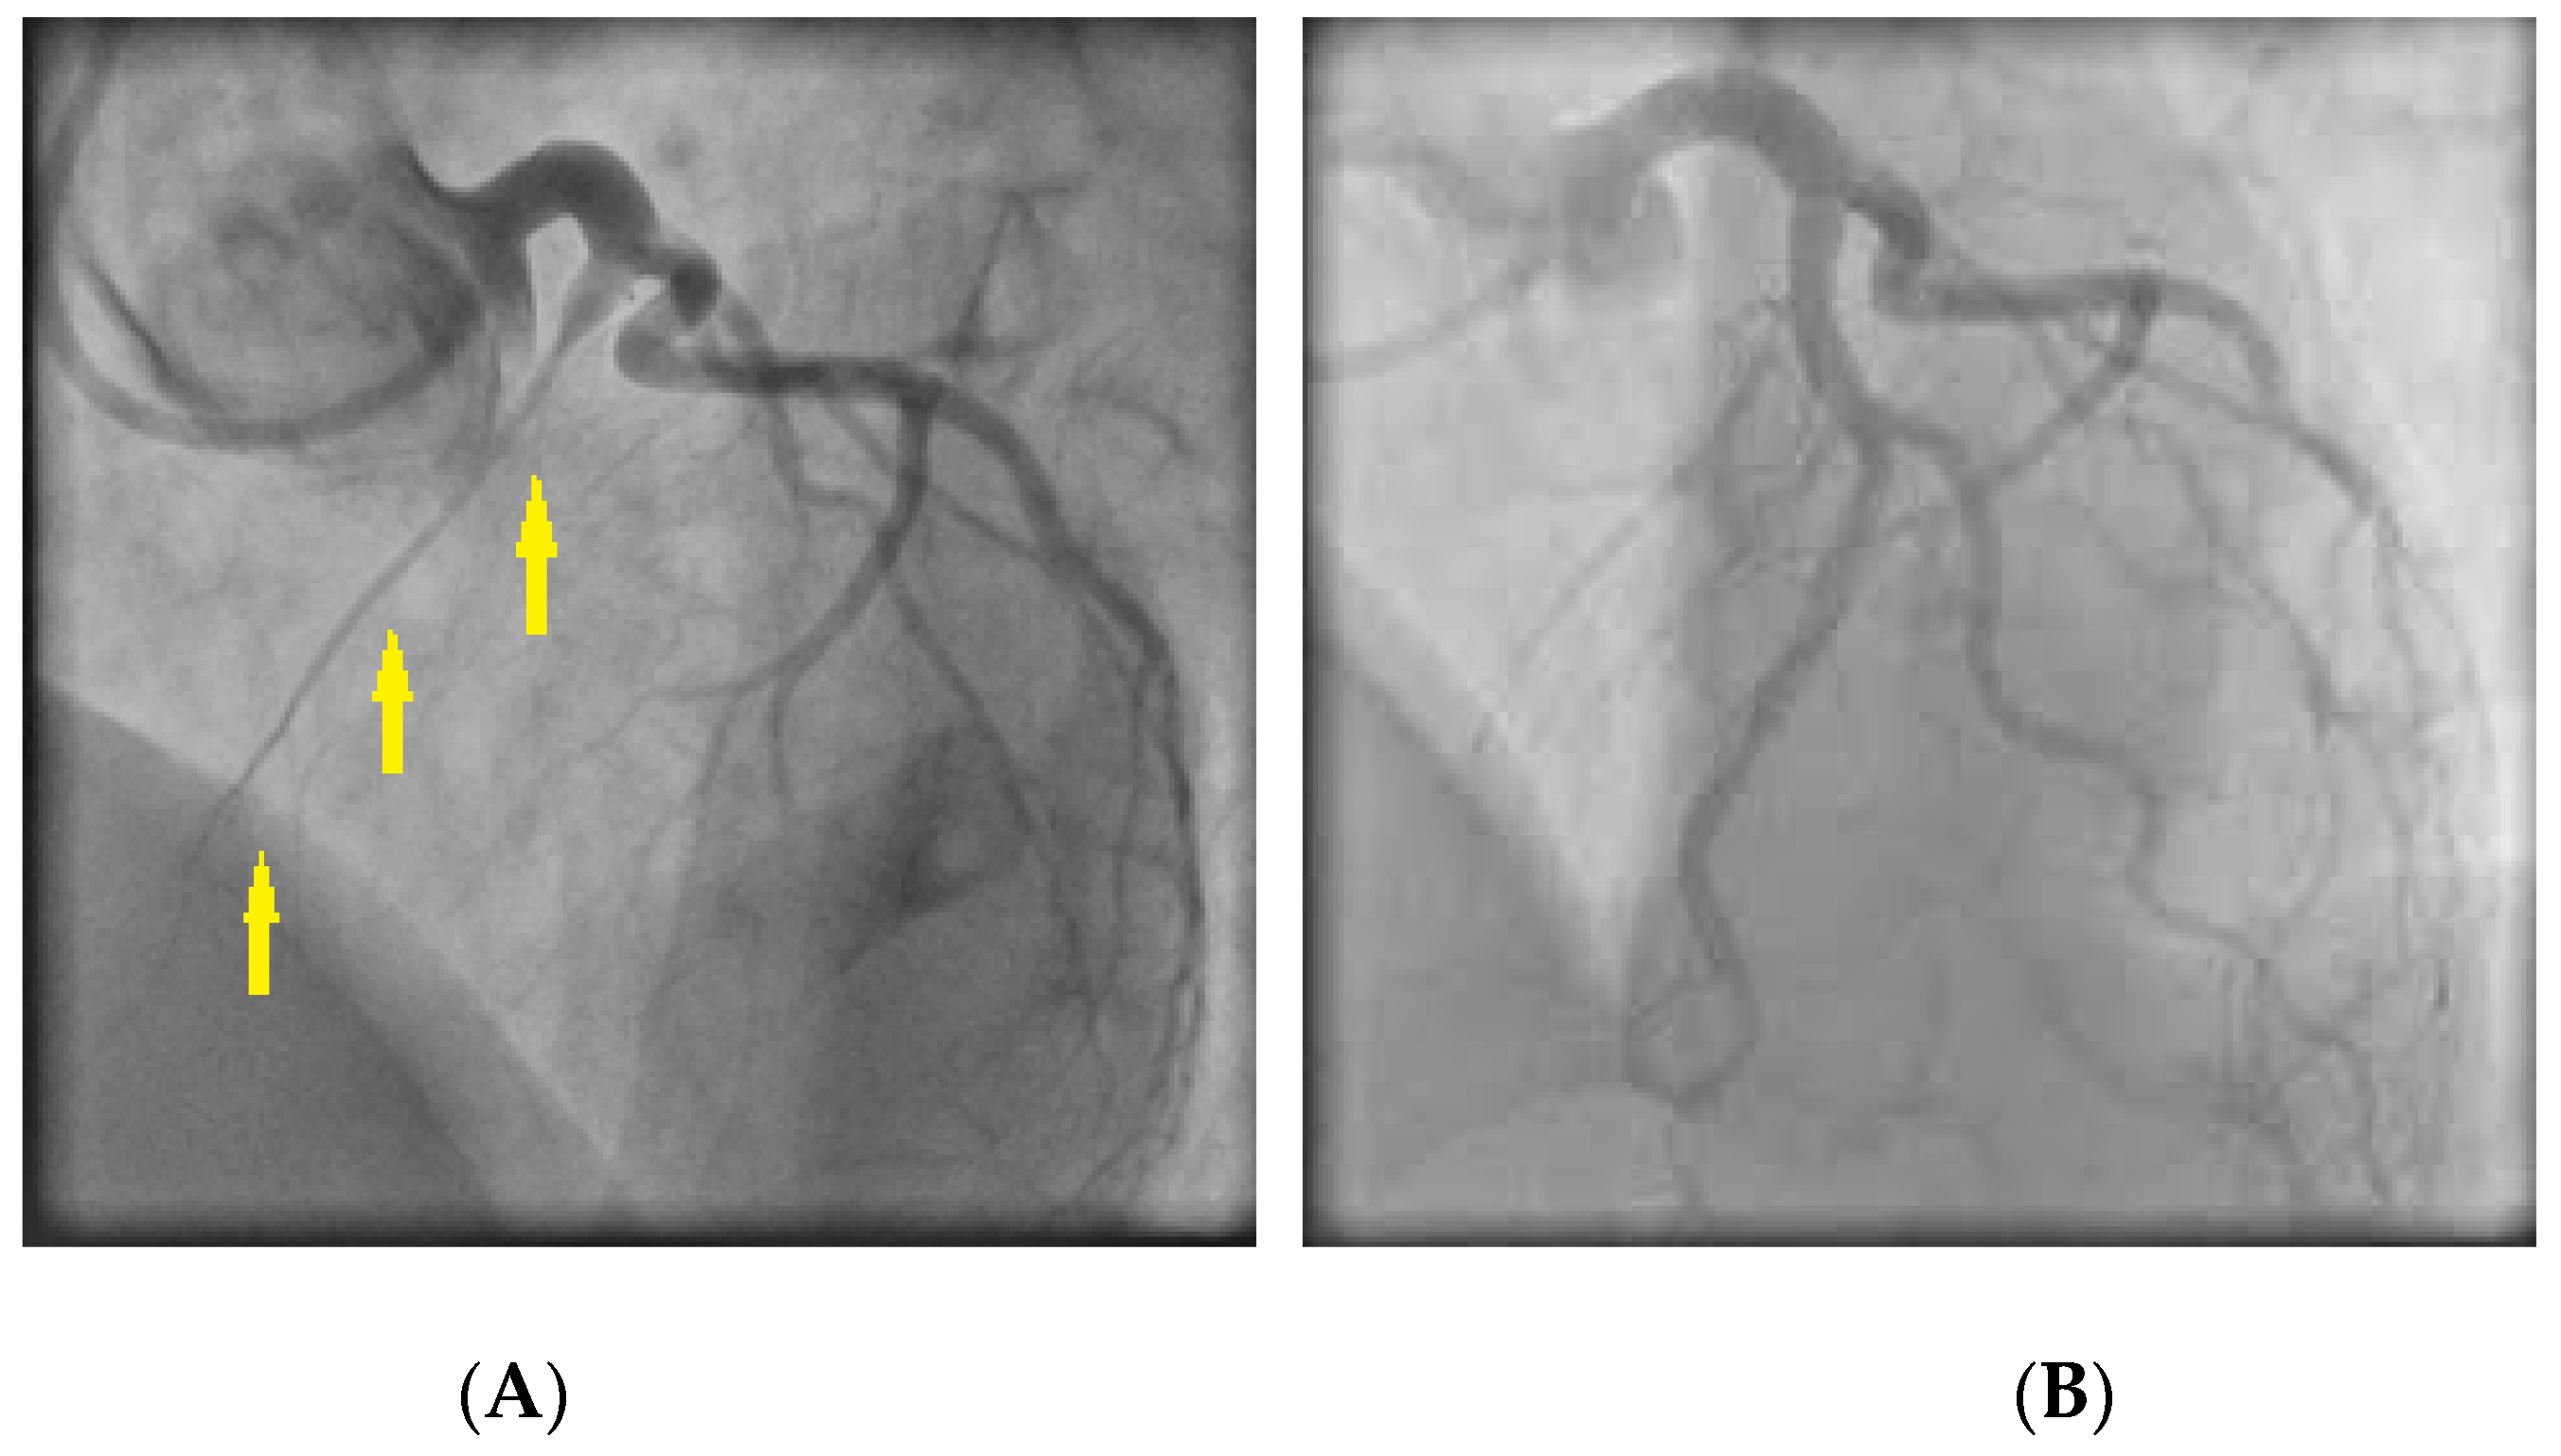

6.1. Spontaneous Coronary Artery Dissection (SCAD)

- Saw, J.; Mancini, G.B.J.; Humphries, K.; Fung, A.; Boone, R.; Starovoytov, A.; Aymong, E. Angiographic appearance of spontaneous coronary artery dissection with intramural hematoma proven on intracoronary imaging. Catheter. Cardiovasc. Interv. 2016, 87, E54–E61. [Google Scholar] [CrossRef] [PubMed]

- Eleid, M.F.; Guddeti, R.R.; Tweet, M.S.; Lerman, A.; Singh, M.; Best, P.J.; Prasad, M.; Rihal, C.S.; Hayes, S.N.; Gulati, R. Coronary artery tortuosity in spontaneous coronary artery dissection: Angiographic characteristics and clinical implications. Circ. Cardiovasc. Interv. 2014, 7, 656–662. [Google Scholar] [CrossRef]